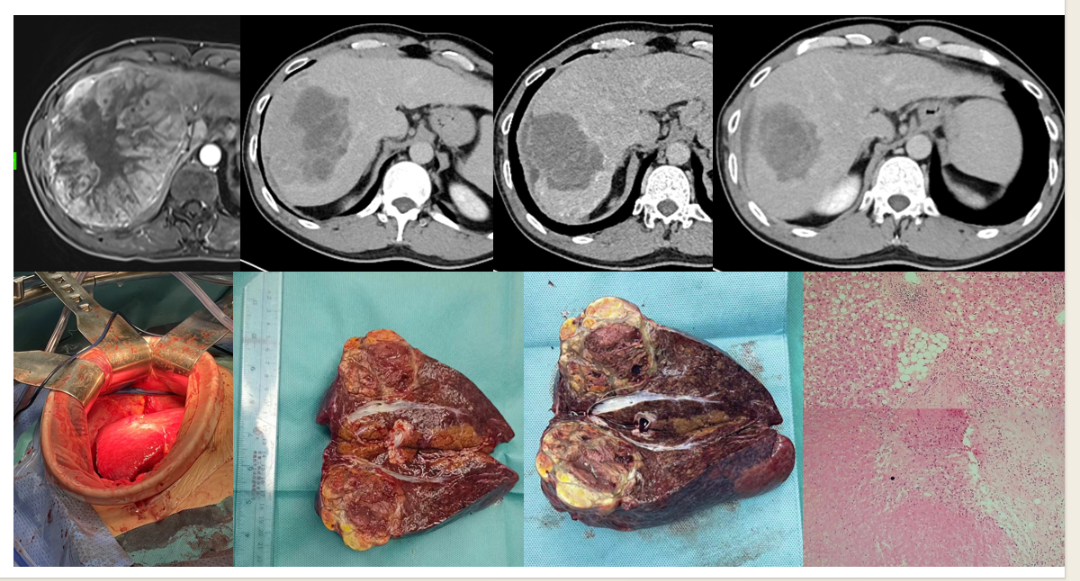

为巨大肝癌桥接手术提供希望

肝部右叶巨块肿瘤占位,大小约16cm×13.3cm×15.1cm,乙肝病史10年多,APF:337ng/ml,肝功能:Child-Pugh A6分。ECOG 体态评分 0 ,诊断:HCC:CNLC分期:IIIb期。因肿瘤体积较大、残余肝体积不足,行钇90树脂微球治疗。术后3个月肿瘤明显缩小,未见明显活性肿瘤细胞,肿瘤萎缩,而正常肝左叶明显增大;于术后5个月,成功进行外科切除。